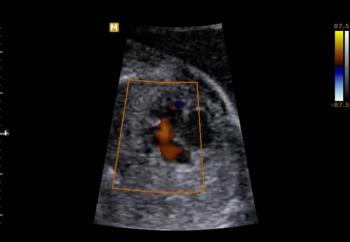

This 18-week fetus has a vascular anomaly. Can you identify it?